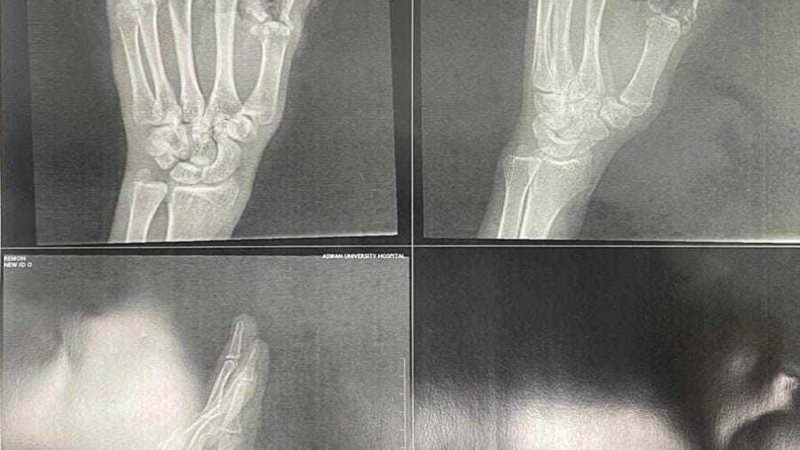

فريق طبي بمستشفى جامعة أسوان ينجح في إعادة أصابع يد شاب بعد بترها

نجح فريق من الجراحين بقسم التجميل بمستشفي جامعة أسوان، في إجراء جراحة دقيقة نادرة لشاب أصيب ببتر في ثلاثة أصابع فى يده اليسرى، من جراء استعماله لساطور نتج عنه قطع الدموية والأوتار والأعصاب والعظام بأصابع اليد، تم إعادة تركيب الأصابع، وإعادة الدورة الدموية لكف اليد مرة أخرى، عقب التدخل الجراحي السريع للتعامل مع الحالة بدقة وعناية فائقة.